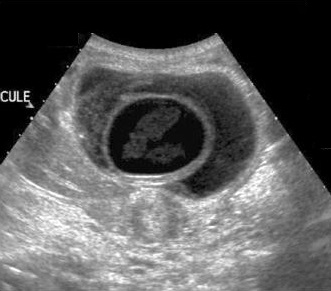

Image echographique du foie : Image

echographique d'une calcul biliaire en C inverse (

fleche rouge) avec zone d'ombre de acoustique

posterieure . Canal hepatique commun et des voies

biliaire intrahepatique sont tres dilatees (

syndrome de Mirizzi ) |